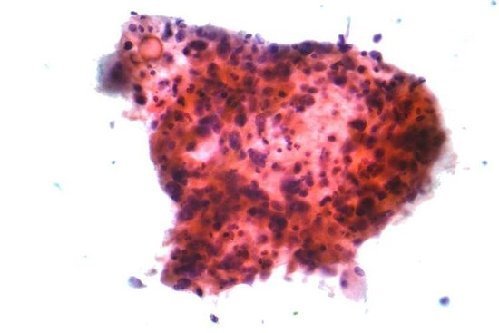

对多种肿瘤有疗效的抗癌药E-75

据国外媒体报道,来自美国陆军部队的专家近日在位于德克萨斯州的圣安东尼奥市军事医疗中心成功研制出一种名为“E-75”的超级抗癌药物,对多种肿瘤的治疗都具有很好的效果。

据了解,研究人员研制这种化学药物最开始的初衷是为了降低乳腺癌的再发率,但在研究的过程中,研究人员却意外的发现这种药物同时还具有其他的功效。因为,那些吞服了这种药物的人们与服用普通控制药物的人们相比,前者患上结肠癌、前列腺癌、肺癌的概率有了明显的降低。

研究人员在实验中选择了一些经基因测试或医疗审定后,被断定为有患上乳腺癌危险的女性,并将其分为两组,一组吞服控制性药物,另一组吞服了“E-75”药物。研究结果显示,吞服“E-75”药物的研究对象的乳腺癌再发率仅有10%,而吞服控制药物的一组竟高达20%。这就意味着超级抗癌药物“E-75”具有着正面积极的保护作用。研究人员之所以会选择这样的研究方法,是因为避免出现类似人们在感染流感后再注射流感疫苗的现象。

研究人员解释说,抗癌药物“E-75”的“工作方式”相对来说较为简单,它能够成功的在人们体内建立一个特有的免疫系统,这种系统能够搜寻、识别以及确认呈现在多种类型癌细胞表面的蛋白质,从而对应的进行免疫。但是并不是所有肿瘤都是由分泌这种蛋白质分子的细胞组成的,这也是为何抗癌药物“E-75”不能治疗目前所有癌症类型的主要原因。而且,抗癌药物“E-75”在人体内所建立的特有免疫系统不能击败所有癌症细胞的主要原因之一,还因为有一些癌细胞具有“欺骗”免疫系统的功能,以至于当免疫系统进行识别时,会把这些癌细胞误认为是人体的一部分。但是一旦免疫系统“揭穿”这些癌细胞的“伪装面具”,它们就会毫不留情的对这些癌细胞进行消灭,不留任何一个“活口”。

但是即便这样,研究人员仍然坚信,只要在该药物的基础上继续进行研究,未来一定会出现治疗癌症的新型药物和治疗方法,它们定会拥有帮助全世界数百万人改善生活质量的巨大潜力。研究人员表示,它们在过去几十年的主要研究任务就是激活该独特的免疫系统,这也是与癌症“战斗”的主要方法之一。该军队的陆军上校补充解释道,现在出现的关键问题是大多数癌症疫苗在被发现时,癌症患者往往已经处于癌症末期或晚期,因此通过直观的方式去检查是没有意义的。